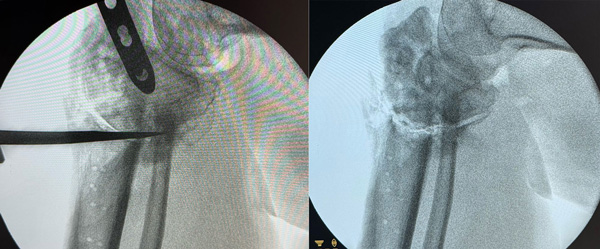

Intra-operative pictures